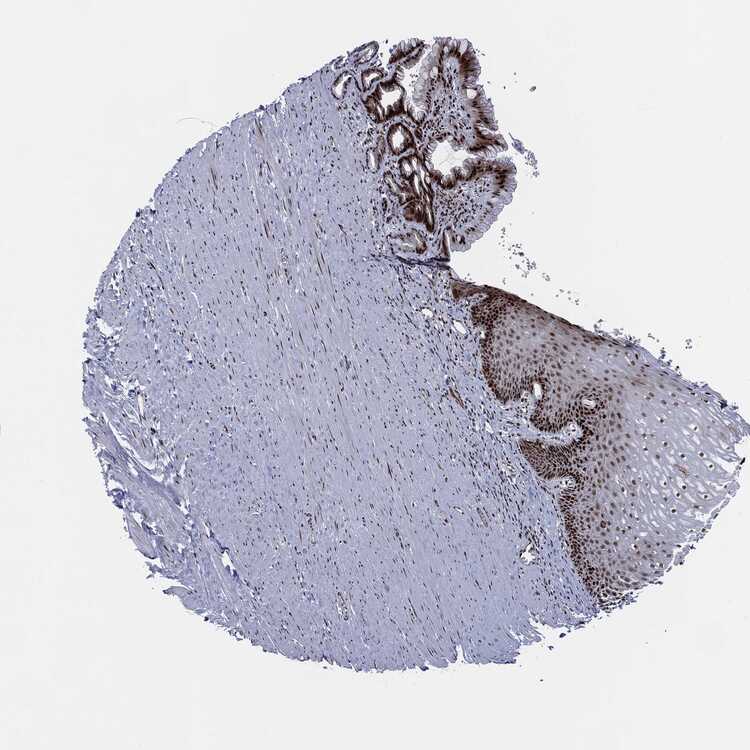

ESOPHAGUS - Antibody stainingi

Antibody staining in the annotated cell types in the current human tissue is reported as not detected, low, medium, or high, based on conventional immunohistochemistry profiling in selected tissues. This score is based on the combination of the staining intensity and fraction of stained cells.

Each image is clickable and will lead to virtual microscopy that enables deeper exploration of all samples and also displays staining intensity scores, fraction scores and subcellular localization as well as patient and tissue information for each sample.

Antibody CAB004204Antibody CAB080295

Squamous epithelial cells LowHigh